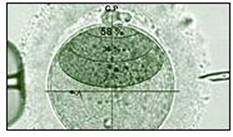

Le Dr. Viot et coll. ont réalisé leur étude dans 33 centres français de PMA, soit environ un tiers du nombre total de cliniques habilitées à effectuer ces interventions. Toutes les naissances par PMA de 2003 à 2007 intervenues dans ces établissements ont été prises en compte, soit 15.162 naissances au total. Cette étude la plus importante réalisée à ce jour sur ce sujet a été effectuée par questionnaires remplis à la fois par les parents et le pédiatre. Elle fait apparaître une prévalence des malformations constatées par rapport aux données générales obtenues à partir des registres nationaux.

"Nous avons trouvé une malformation congénitale majeure chez 4,24% des enfants», a déclaré le Dr Viot, "à mettre en regard des 2-3% estimés par les précédentes études publiées. Ce taux plus élevé est lié en partie à un excès de maladies cardiaques et de malformations du système uro-génital qui interviennent de manière plus fréquente chez les garçons. Parmi les malformations mineures, nous avons identifié 5 fois plus d'angiome soit des tumeurs bénignes composé de petits vaisseaux sanguins sur la surface de la peau. Ces malformations mineures interviennent, en revanche, 2 fois plus souvent chez les filles que les garçons. "